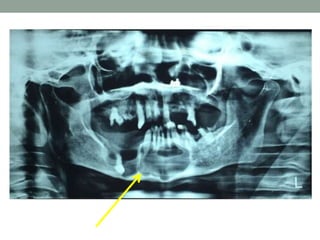

Radiographic Features

• OKC demonstrate a well-defined radiolucent area with

smooth and often corticated margins. Larger lesions tends

to be multilocular.

• Radiography:

OPG was advised which showed, multilocular radiolucency

extending from right rams-angle region to mandibular anterior

region with well defined sclerotic border without roots resorption

and thinning of cortical plates and only few mm of mandibular lower

border remaining.

Investigations • Aspiration ofcystic contents: Showed dirty pus colored fluid, contained shredded and fragmented cells of cystic lining. • Protein analysis: Toller postulated that a protein level of less than 4.0 gm/100ml indicated a diagnosis of OKC. • Radiography: OPG was advised which showed, multilocular radiolucency extending from right rams-angle region to mandibular anterior region with well defined sclerotic border without roots resorption and thinning of cortical plates and only few mm of mandibular lower border remaining.

Radiographic Features • OKCdemonstrate a well-defined radiolucent area with smooth and often corticated margins. Larger lesions tends to be multilocular. • Sometimes associated with unerupted tooth mimicking dentigerous cyst. • Root resorption is common.